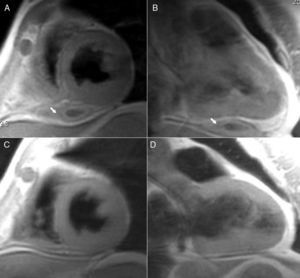

He had suffered a blunt chest trauma several months before while working. At that time, echocardiographic analysis revealed a moderate pericardial effusion which was treated with anti-inflammatory drugs. His clinical evolution was good but echocardiographic study revealed signs of constriction. Cardiac MRI was performed 11 months after the chest trauma and revealed an intrapericardial diaphragmatic mass which was compatible with an organized pericardial hematoma (Figure 1, panels A and B, arrows) with no signs of pericardial constriction. As the patient was asymptomatic, it was decided to perform periodic follow-up only.

Control cardiac MRI 18 months later (Figure 1, panels C and D) revealed considerable improvement, with complete resolution of the hematoma and with slight pericardial thickening as a residual lesion.